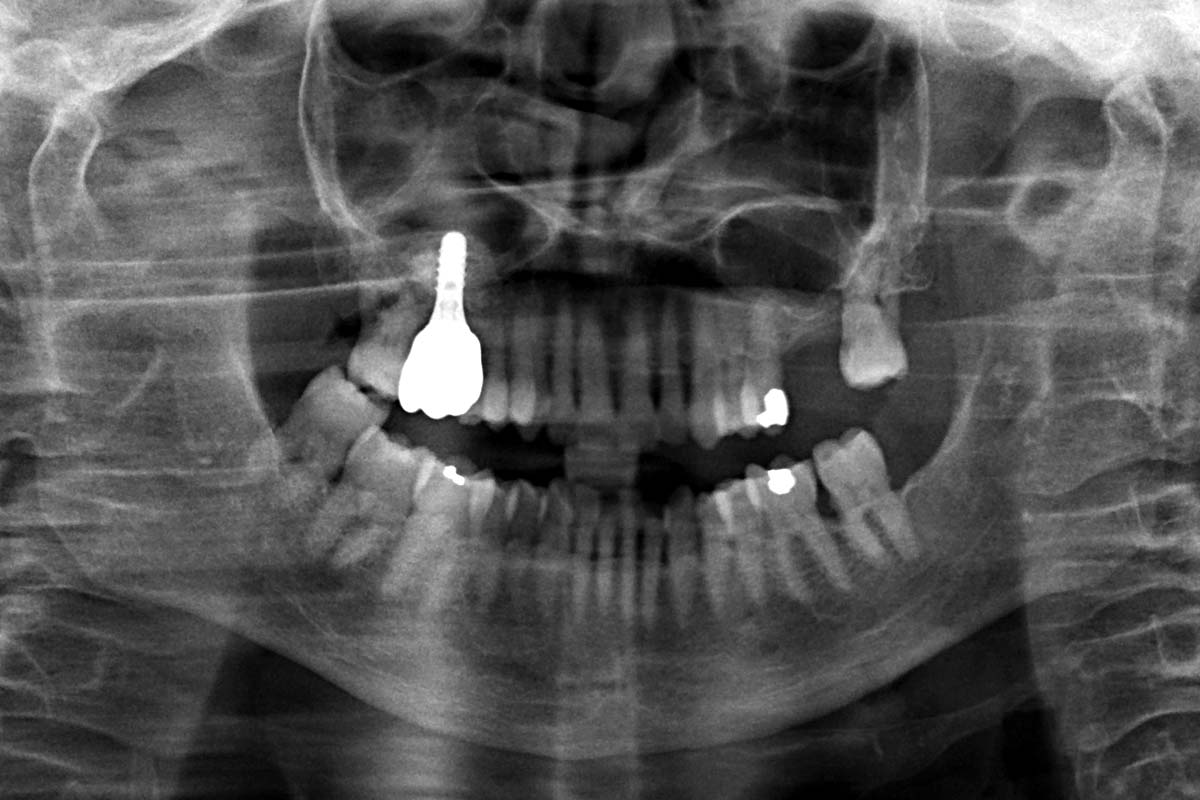

11/11 - X-Ray control 2 years after implant placement and 1 year after final restorationMaxillary sinus augmentation with cerabone® plus - Dr. J. Gargallo-Albiol